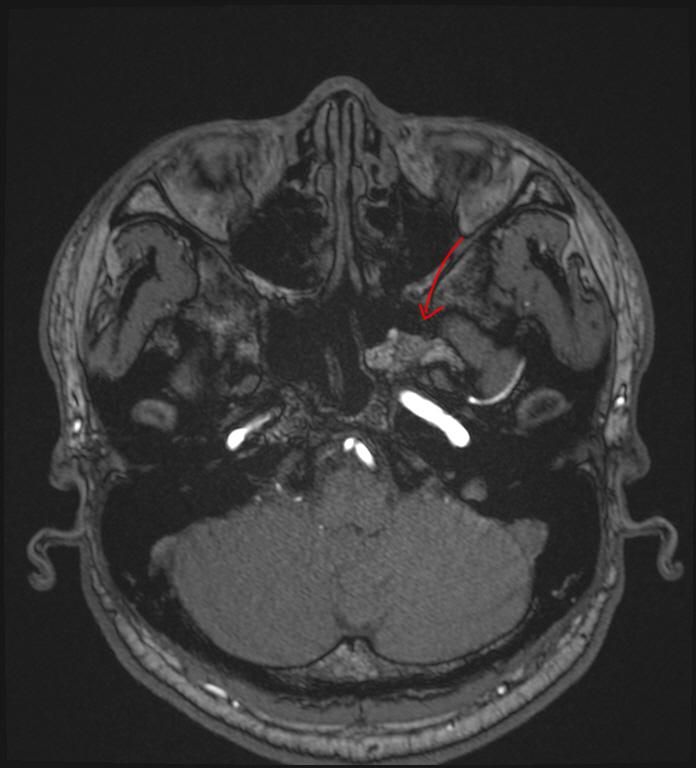

mri 사진을 봤을 때 정확히 어디가 막힌 걸까요? 그리고 치료는 할 수 있는 걸까요???

• 2번 째 사진

올려주신 영상 관련 보다 더 자세한 분석 원하시면 영상의학과 전문의한테 물어보셔야 해요

말씀하신 증상 관련 답변 드리자면 15년동안 지속된 귀와 코 사이 막힘 증상은 이관(유스타키오관) 기능 장애일 가능성이 높습니다. 진한 콧물을 강하게 들이마신 후부터 증상이 생겼다면, 이관이 분비물이나 압력 변화로 막히거나 손상되었을 가능성이 있습니다. 이관은 코 뒤쪽과 귀 중이를 연결하는 통로로, 막히면 귀먹먹함, 압력감, 울림 증상 등이 지속될 수 있습니다. MRI나 CT를 통해 이관 주변 구조(비인두, 부비동, 중이강 등)의 해부학적 이상을 더 정확히 확인해야 합니다.